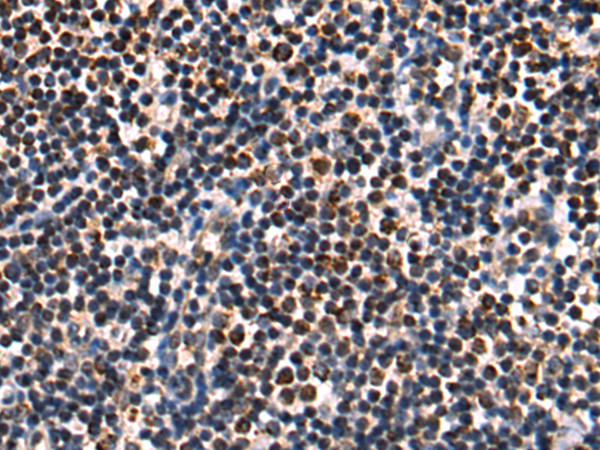

分类: 科研抗体货号: P00260别名: KIP1; MEN4; CDKN4; MEN1B; P27KIP1应用: IHC反应种属: Human, Mouse